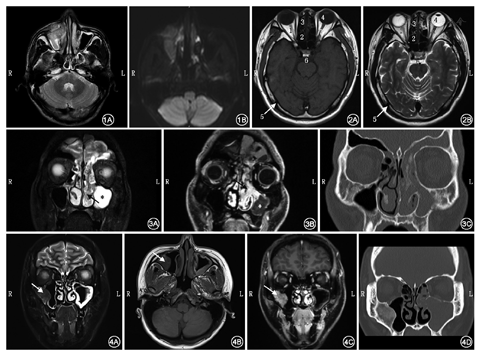

脉冲序列是指射频脉冲、梯度场和信号采集时间等相关扫描参数的设置及其在时序上的排列,不同的脉冲序列组成了MRI的检查技术。常用的MRI检查技术包括MR血管成像(MR angiography,MRA)、MR水成像(MR hydrography)、脂肪抑制技术、磁化传递成像(magnetization transfer contrast,MTC)和MR功能成像(functional MR)等。MRA具有不需要对比剂、无创、简单及可重复等优点,因此应用广泛,如颅脑血管成像、颈部大血管成像等。增强MRA是利用顺磁性物质(对比剂,常用为钆喷酸葡胺)使血管内血液的T1值呈显著高信号,血管外其他组织相应呈低信号而进行的重建,主要应用于动脉瘤、假性动脉瘤、深静脉血栓等血管性病变。肿瘤强化的原理是静脉注射对比剂后,对比剂可弥散到血管外组织间隙,改变局部磁场环境,肿瘤早期增强取决于肿瘤富含血管的程度,而晚期增强取决于血管对造影剂的通透性。MR水成像利用水具有长T2的特性,通过后处理使之显示出高信号,可应用于内耳疾病、脑脊液漏等。MR脂肪抑制技术主要应用于周围脂肪组织较多的病变或组织,如眼眶、骨髓区域的肿瘤。在MRI增强图像上脂肪为高信号,肿瘤增强后也为高信号,难以鉴别;抑制脂肪信号后,比较容易判断肿瘤是否侵犯了眶脂肪和骨髓。MTC是近几年来推出的MR成像新技术之一。体内氢质子的存在形式分为两种:一种存在于自由水和某些含脂肪组织的氢质子呈现自由运动状态,具有较长的T2值;另一种氢质子呈运动受限状态,包括那些结合在大分子物质如蛋白质、碳水化合物、核酸、脂类以及细胞膜上的氢质子,其T2值极短,普通MRI不能有效显示。MTC通过直接化学交换和偶极交联等机制与体内氢质子间存在磁量交换,可以形成组织特异性的T1值和T2值,有效调节组织对比度,改善病灶的显示情况。MR功能成像有多种,包括弥散加权成像(diffusion-weighted imaging,DWI)、扩散张量成像(diffusion tensor imaging,DTI)、灌注加权成像(perfusion-weighted imaging,PWI)等。在均质的水中,如不设定范围,水分子的流动扩散是一种完全随机的热运动,但在人体中,水分子只能在有限的范围内活动,即各向异性。在梯度磁场下,水分子运动的各项异性显示为不同的表观扩散系数(ADC),DWI信号强度与ADC图信号强度相反。以前DWI常用于缺血性颅脑疾病的诊断,近期研究发现其对于肿瘤亦有重要诊断意义。恶性肿瘤细胞密集、细胞间隙狭窄,其阻挡作用抑制了水分子的扩散,导致ADC值很小,在ADC图上呈现低信号;而肿瘤内的坏死囊变部分细胞结构疏松,水分子扩散阻力减少,在ADC图上呈现高信号(图1)[1]。

了解鼻腔鼻窦正常结构在MRI上的表现对发现病变非常重要。鼻窦是4对含气空腔,从表面到深部由多种组织构成,包括黏膜上皮、血管、神经、软骨、骨、淋巴组织等;周围包括眼眶、口腔、颅底等区域,MRI信号多种多样,以自旋回波序列为例,这些正常组织的T1WI和T2WI信号(与脑灰质信号相比较)总结如下(表1,图2)。

虽然欧洲鼻腔鼻窦肿瘤内镜诊疗意见书中推荐CT为SNIP术前的常规检查[2],但目前研究认为MRI可很好地鉴别肿瘤与炎性组织,降低SNIP误诊率,有利于寻找肿瘤的基底部,确定手术进路和判断术后复发,尤其是针对起源于额窦的SNIP[3]。SNIP的MRI表现为单侧鼻腔鼻窦肿块,T1WI呈等、低信号,T2WI呈等、高信号,增强时伴不均匀强化。尤其值得注意的是,在T2WI或增强T1WI上,SNIP实体呈等信号或轻度增强的"脑回征",病变内部结构多呈较规整的栅栏状、卷曲脑回状。 "脑回征"由平行排列、高和等信号相间的条状影构成,与组织学对应:前者对应水肿的间质(少细胞),T2WI为高信号粗条影,因其血管丰富,增强后明显强化;后者对应增生的上皮(多细胞),T2WI为等信号细条影,增强后轻度强化。 "脑回征"是SNIP在MRI上的特征性表现,阳性率达95%以上(图3)。当CT怀疑骨质破坏时,行MRI-DWI检查有助于判断SNIP是否伴有恶性变,伴恶性变的肿瘤ADC值更低(1.12×10−3mm2/s),与良性者(1.49×10−3mm2/s)比较差异有统计学意义[4,5]。而CT仅可提示鼻窦单侧软组织病变,局部骨质增生提示可能为肿瘤基底部,但是对于鼻窦内的软组织影,不能鉴别肿瘤或炎症,且难以判断复发病例的肿瘤基底部。

骨化纤维瘤和骨纤维异常增殖的影像学诊断主要依靠CT检查,但当肿瘤涉及视神经、颅底、眼眶时,推荐术前行MRI检查,因为MRI可评估视神经因肿瘤压迫而出现的水肿、萎缩[6],以及是否存在脑组织压迫、水肿等。这类骨性病变可分为硬化型、囊性和混合型。骨纤维异常增殖的信号特点取决于肿瘤组织内骨小梁和胶原蛋白含量[7],骨小梁结构含量越多,T2WI信号越低,反之亦然。有部分的骨化纤维瘤内部呈囊性变,MRI可见T2WI高信号、T1WI等信号。绝大部分的肿瘤增强后实性部分显著强化(图4)。

鼻咽纤维血管瘤好发于青少年男性,CT检查可提供术中所需的解剖标志,但MRI对判断肿瘤的范围、边界、侵犯翼腭窝、颞下窝、眶下裂、翼管和圆孔的程度、肿瘤血供情况有重要作用,特别对于复发的病例。若肿瘤与周围软组织粘连,MRI更有助于分辨病变与正常组织。原发的鼻咽纤维血管瘤在增强MRI中表现为起源于蝶腭孔或翼管的不均质肿块,T1WI、T2WI混杂信号,肿块内见多量流空血管影,增强后呈均匀显著强化[8]。肿瘤可向外侧突入翼腭窝、颞下窝和眶下裂,向上方突入蝶窦、筛窦、圆孔和海绵窦,向下方自后鼻孔突入鼻咽腔,向后方突向翼管、翼突根部和翼内外板之间,到达颈内动脉前方和破裂孔。MRA及CE-MRA可判断肿瘤血供情况,大部分的鼻咽纤维血管瘤血供来自于颌内动脉和咽升动脉,若肿瘤突向上生长则可能由颈内动脉及颈外动脉的分支共同供血,也可能由对侧的颈内和颈外动脉供血。在这种情况下,增强MRA对判断是否需行术前DSA栓塞、如何栓塞、手术风险、手术难度有很大帮助。

鳞状细胞癌和腺癌好发于中老年患者,大部分起源于上颌窦,其次为鼻腔、筛窦,软组织肿物伴骨质破坏是其CT特征表现[8],但CT能够提供的信息非常有限,MRI平扫+增强是常规的检查方法。这两种肿瘤在MRI上表现为T1WI等或稍低信号,T2WI等或稍高信号,增强呈不均匀强化,提示局部可能有坏死、出血(图5)。大部分鳞状细胞癌和腺癌破坏周边骨质,T1增强抑脂序列对判断眶内、颅底侵犯,以及神经、肌肉侵犯有重要作用。当肿瘤侵犯骨质时,T1WI上骨髓高信号被肿瘤取代表现为低信号。若肿瘤突破硬脑膜及蛛网膜,在T2WI上表现为脑组织周围高信号的脑脊液被等信号软组织肿瘤侵犯。腺癌的MRI信号取决于黏液含量、是否伴瘤内出血和细胞结构,黏液含量高的腺癌表现为T2WI高信号,黏液含量低的腺癌表现为T2WI等、稍高信号。

嗅神经母细胞瘤是起源于嗅上皮(神经内胚层)的恶性肿瘤,常见肿瘤中心位于筛板、上鼻甲和鼻中隔上1/3。嗅神经母细胞瘤发病年龄范围广,但具有20岁和60岁两个高峰[12]。嗅神经母细胞瘤常直接侵犯鼻窦、筛板、颅底和眶,疾病进程中常出现颈部淋巴结转移(20%~25%)和远处转移(10%~40%)。MRI上表现为T1WI较灰质信号低、T2WI较灰质信号高的肿块[13],增强后除坏死和出血外呈均匀强化(图6)。

恶性黑色素瘤是来源于色素细胞的恶性肿瘤,在黏膜恶性黑色素瘤中,鼻腔鼻窦为第二好发部位。侵犯黏膜的恶性黑色素瘤恶性程度高,根据美国癌症联合委员会(AJCC)分期,未侵犯骨质的为T3肿瘤。恶性黑色素瘤可分为黑色素型和无色素型,色素含量在某种程度上决定其在MRI中的表现,典型的黑色素型肿瘤T1WI呈高信号,T2WI呈等、低信号,而无色素型表现为T1WI低信号、T2WI高信号,增强MRI呈轻到中度强化(图7)[14]。